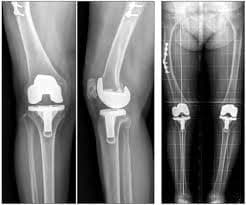

Хиймэл үе суулгасаны дараах байдал

Рентген, эгц урдаас харуулсан байдал

Рентген, хажуугаас харуулсан байдал